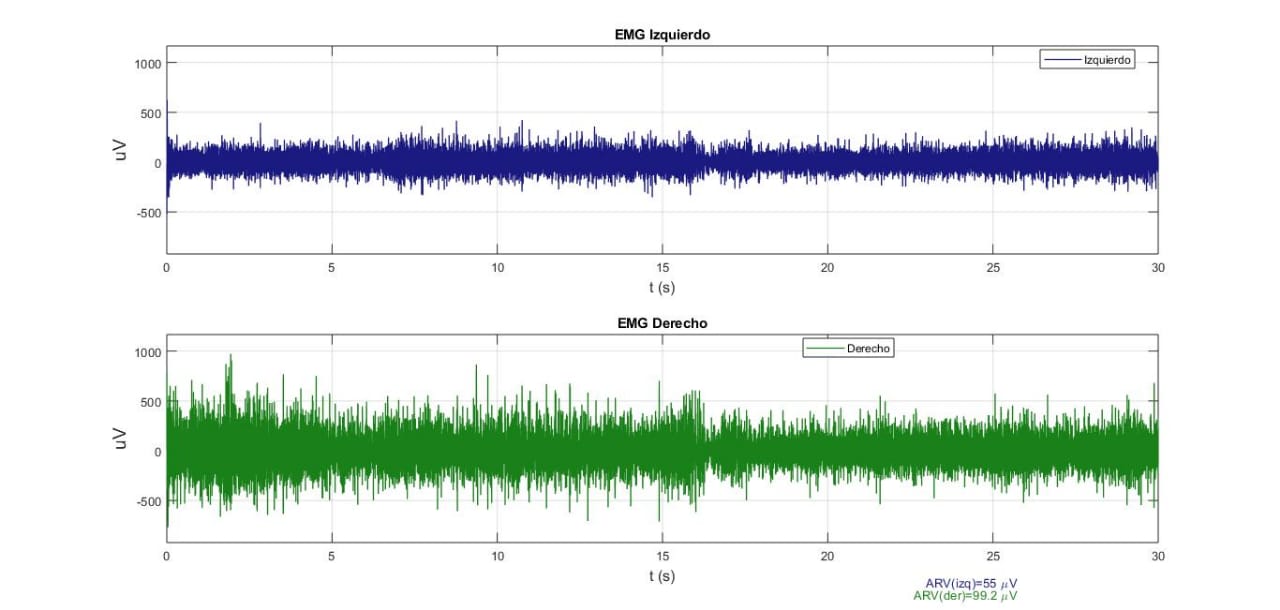

Señal EMGS cruda registrada durante contracción isométrica en oclusión centrica (OC), (Laboratorio de fisiología oral, 2019)